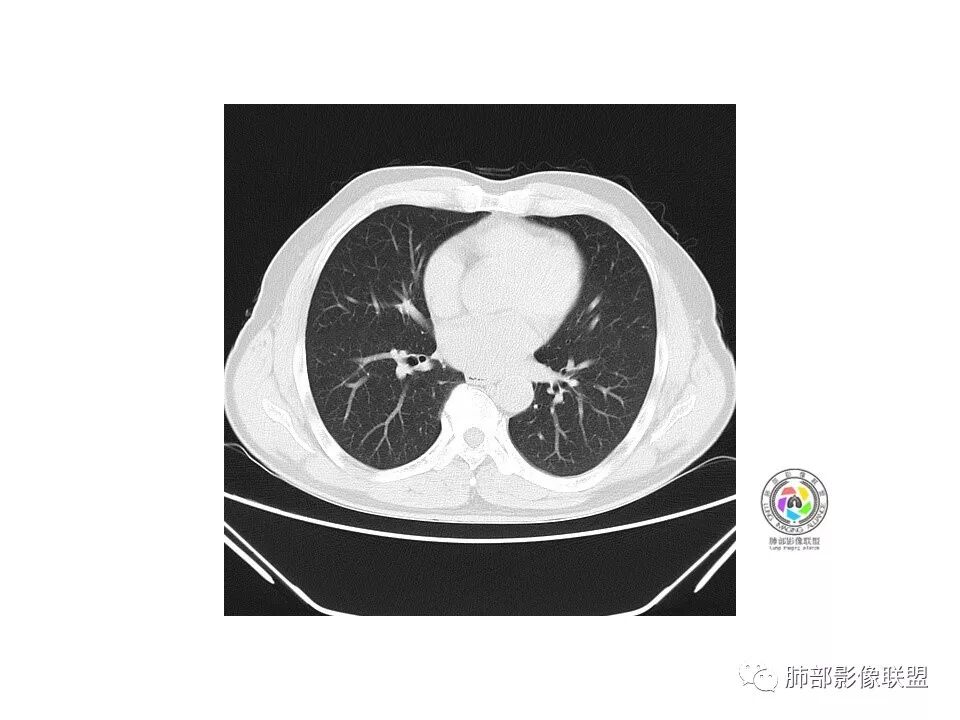

右肺下叶见边界清晰混合磨玻璃密度影,目测内见实性结节小于5mm,有浅分叶,前缘小叶间隔阻挡,月牙铲?胸膜牵拉,老年患者,MIA可能,鉴别炎性病变,抗炎后复查

患者老年男性,以咳嗽 、咳痰3天就诊,胸CT:右肺下叶前基底段mGGO,内可见血管形态改变,细支气管扩张,病灶边界清,边缘可见月牙铲。考虑恶性,腺癌?但建议先抗炎治疗后复查

老年男性、咳嗽咳痰三天,右下前基底段GGN,血管影增多,伴类似的树芽,边缘稍模糊,考虑结核。

右肺下叶磨玻璃结节,密度不均,边缘收缩,胸膜牵拉,考虑炎性,建议复查,除外腺癌。

右肺下叶混合磨玻璃结节,边缘清晰,浅分叶,月牙铲,胸膜牵拉,血管进入,考虑MIA可能,鉴别炎性病变

磨玻璃结节,边缘清楚,浅分叶,月牙铲,考虑腺癌可能,抗炎后复查。

右肺下叶混合磨玻璃密度结节影,局部胸膜牵拉,月牙铲,考虑腺癌

磨玻璃小结节,有明显收缩性表现,胸膜凹陷,考虑腺癌

患者老年男性,咳嗽  咳痰3天就诊。胸部CT:右肺下叶前基底段混合磨玻璃结节,边缘清楚,可见毛刺、胸膜牵拉、血管集束、月牙铲征象。综合考虑微浸润腺癌可能大。

右肺下叶前基底段混合磨玻璃结节,边界清,浅分叶,胸膜牵拉,月牙铲,血管进入,考虑:微浸润腺癌可能性大,抗炎后复查。

老年男性,右下叶孤立ggo,先抗炎2-3周复查,无变化→切,小了→炎性

40岁以上男性,孤立混合磨玻璃,边界清楚,分叶,胸膜凹陷,血管集束、穿行,考虑腺癌。

右肺下叶孤立混合磨玻璃结节,隐约细小毛刺,似有月牙铲,胸膜稍牵拉,考虑MIA(微浸润腺癌)可能,常规飞一下。